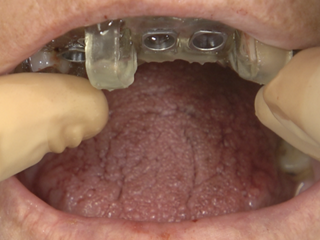

• Passive-fit check of the surgical guide before drilling.

• Temporary bridge pre-fit check using the prosthetic guide and fixation pins.